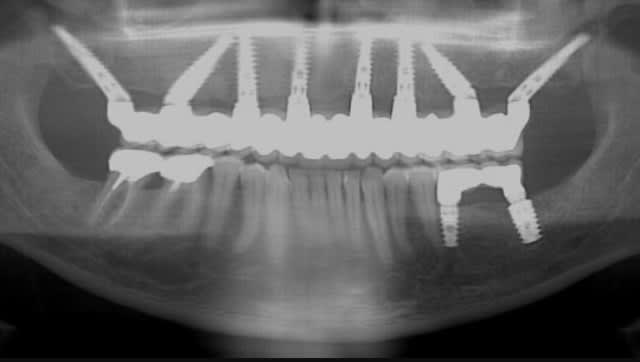

est ce que sur la pano que je poste ces Implants postérieurs sont dans l'axe ? 😊 Est ce que ça pose problème ? J'ai pas l'impression 😊😊😊. Alors tu vas peut être me dire que c'est différent : on est dans des divergences d'axe dans le sens mesio-distal et non vestibulo lingual. Mais Ils ne sont pas tout à fait dans l'axe des dents on dirait, non ? Alors si on extrapole est ce que la ptite divergence d'axe dans un cas comme Le mien pose problème alors qu'au départ il n'y avait quasi pas d'os , ni en largeur ni En hauteur...

Img 1371 bdvvba - Eugenol